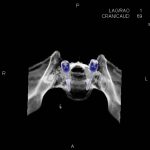

- Diagnosticul fracturilor:

- Unice

- Multiple

- Cu înfundare

- Complexe cranio-sinusale

- Complexe cranio-etmoidale

- Complexe cranio-orbitare

- Complexe cranio-faciale